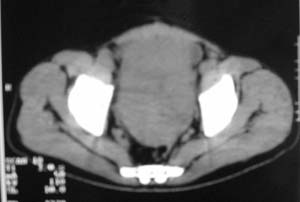

以下是引用zjzjr在2007-9-27 22:20:00的发言:[br]肠腔受推移,未见明显扩张及液平,所以考虑是肠外病灶, 间叶源性肿瘤?脂肪瘤?建议增强。

以下是引用guzhongliangddd在2007-9-27 23:21:00的发言:[br][br]与肠内高密度相同,病灶应该没有钙化,我认为首先考虑是间叶组织的良性肿瘤。建议楼主做后重建观察。中线区域大血管旁未见确切增大淋巴结。病灶对肠道只是推移关系。

以下是引用余辉在2007-9-27 22:24:00的发言:[br]暂考虑肠道间质来源肿瘤如小肠平滑肌肉瘤/瘤可能,应该增强